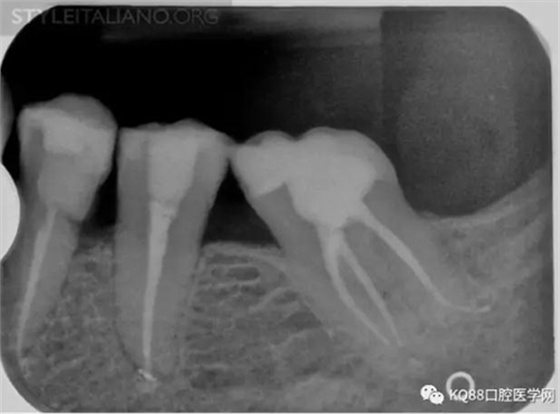

Case 1: In this patient, persistent pain was present after endodontic treatment of a vital tooth. The periapical x-ray showed an inadequate shaping of the distal root canal, regarding both the working length and the apical taper.

Img. 2 - Retreatment of distal canal was performed using ProTaper retreatment files. Working length was assessed electronically. Canal was shaped with a Reciproc R40, thoroughly irrigated with US activation, filled with corresponding Guttafusion obturator. Pain disappeared completely some days after retreatment. In all likelihood, incomplete preparation allowed residual pulp tissue to remain in the root canal, acting as an irritant.